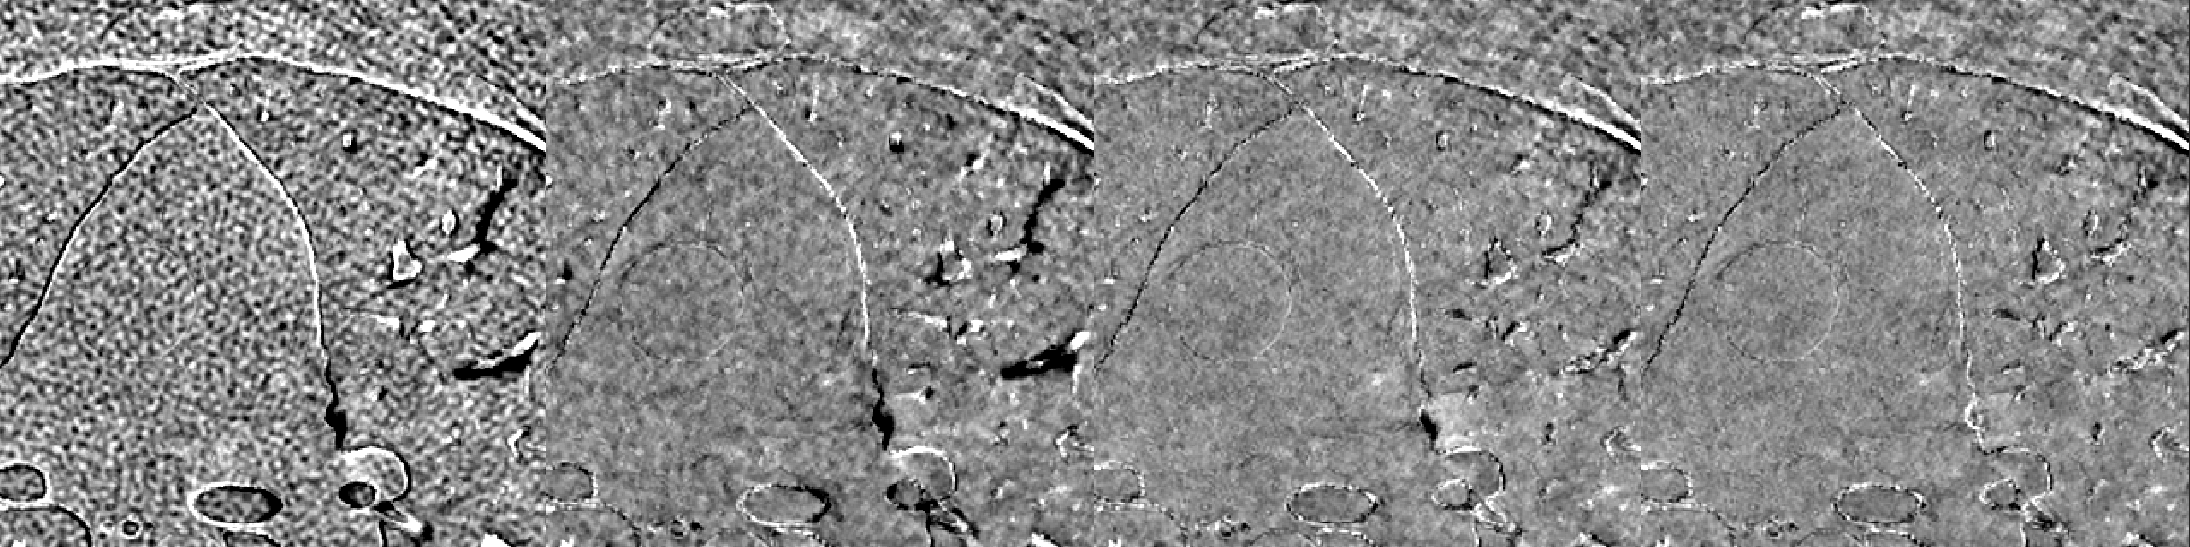

A cardiac FBP image was inferenced on the trained DL-MBIR network. Inference time for every network was between 4 and 6 seconds, and it goes up with the increase in the number of input channels. The MBIR version of the same exam was also available. Figure 3 shows a comparison, for 4 slices – LABEL:sub@fig:Image_10, LABEL:sub@fig:Image_50, LABEL:sub@fig:Image_90, and LABEL:sub@fig:Image_170 in the image volume, among MBIR image, FBP image, and the outputs of DL-MBIRZ𝐷𝐿-𝑀𝐵𝐼subscript𝑅𝑍DL\text{-}MBIR_{Z}, where Z=1, 3, 5𝑍135Z=1,\ 3,\ 5. Figure 4 shows a comparison, for the same slices in the image volume, among difference between images and the MBIR images. Figure 5 has a profile plot to show the comparison of DL-MBIRZ𝐷𝐿-𝑀𝐵𝐼subscript𝑅𝑍DL\text{-}MBIR_{Z} and FBP images w.r.t the MBIR images.

Figure 4: Difference image w.r.t. MBIR. (left to right): FBP𝐹𝐵𝑃FBP, DL-MBIR1𝐷𝐿-𝑀𝐵𝐼subscript𝑅1DL\text{-}MBIR_{1}, DL-MBIR3𝐷𝐿-𝑀𝐵𝐼subscript𝑅3DL\text{-}MBIR_{3}, DL-MBIR5𝐷𝐿-𝑀𝐵𝐼subscript𝑅5DL\text{-}MBIR_{5}. LABEL:sub@fig:Error_10, LABEL:sub@fig:Error_50, LABEL:sub@fig:Error_90 and LABEL:sub@fig:Error_170 represent different slices in the image volume. WW/WL 150/0 HU.

Visually, all DL-MBIR images bear close resemblance to the MBIR images in figure 3. It is confirmed by the difference images in figure 4. In the profile plot of Figure 5, the DL-MBIR profiles closely follow that of MBIR.